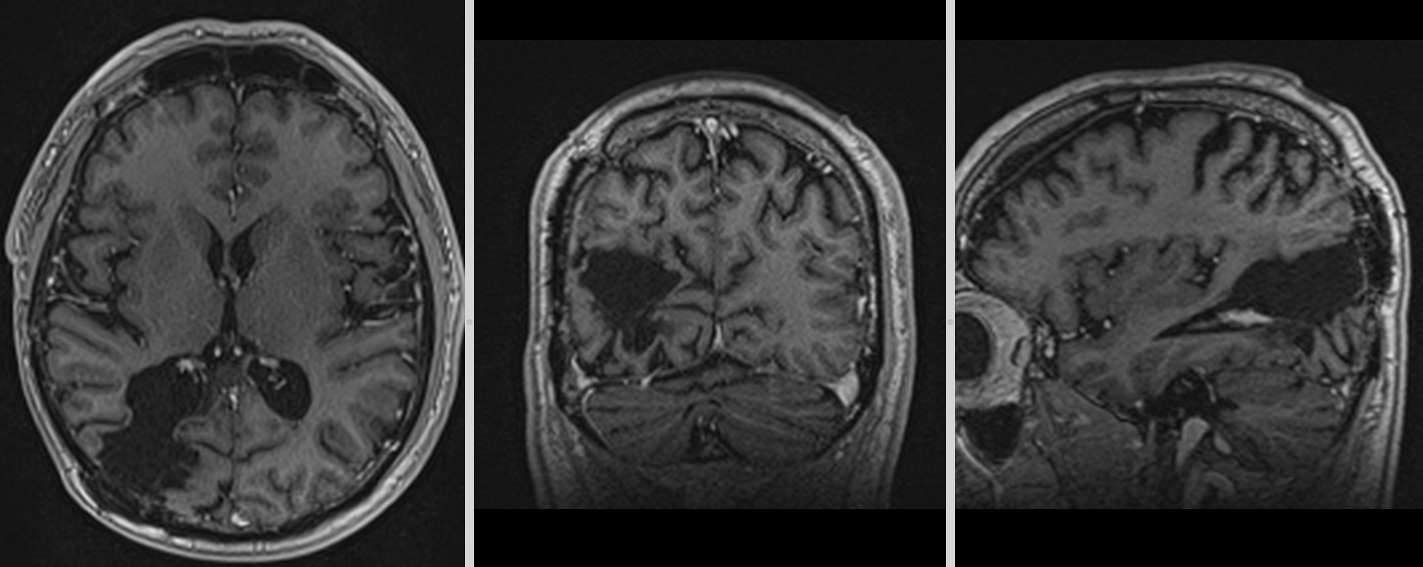

Controalele imagistice s-au repetat periodic, fiecare RMN fiind un moment de emoție și speranță.

Astăzi, la 9 ani de la operație, nu există semne de recidivă tumorală. Deficitul vizual s-a stabilizat, iar dificultățile de recunoaștere a fețelor s-au ameliorat parțial. Mai important însă, pacientul și-a recâștigat viața de zi cu zi.